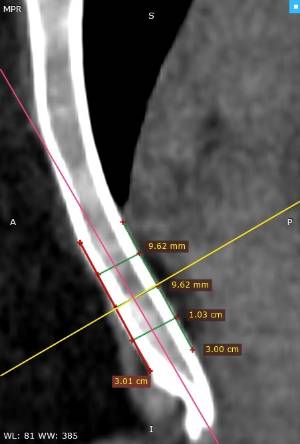

Los datos médicos del paciente, más la exploración clínica realizada por el equipo de cirugía, junto a un análisis pormenorizado de las imágenes del TAC y las reconstrucciones digitales en 3D de cada tórax realizadas conjuntamente con el equipo de ingenieros de Ventura Medical Technologies, son la base para determinar si la técnica Pectus Up está indicada y como se debe proceder en cada uno de los pacientes.

Con estos datos se selecciona el implante que mejor se ajustar a la anatomía de cada tórax, la ubicación exacta del sistema de elevación y, a su vez, proporciona al equipo quirúrgico un detalle de los pasos a tener en cuenta para llevar a cabo una correcta implantación.

Pectus Excavatum Pectus Excavatum Asimétrico Índice de Asimetría 0.6 (+R/-L)(|AI|> 0.05 Asimétrico) Índice de Haller 4.5 (HI >3.5) Índice de Corrección 49.13% Rotación esternal 18.1 ° (a la derecha)

Informe de evaluación del TAC de un paciente enviada al cirujano